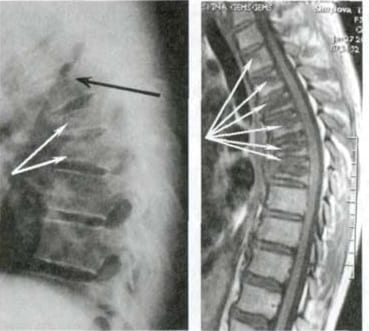

Mujer de 52 años. Desplazamiento y deformación severa del disco intervertebral, compresión de los nervios y daño a la médula espinal.

"Joroba de viuda" — deformación de las vértebras y dolor crónico, insoportable, que se intensifica cada día.

Hernia de disco intervertebral, compresión de los nervios, pérdida de sensibilidad y parálisis parcial de las piernas.